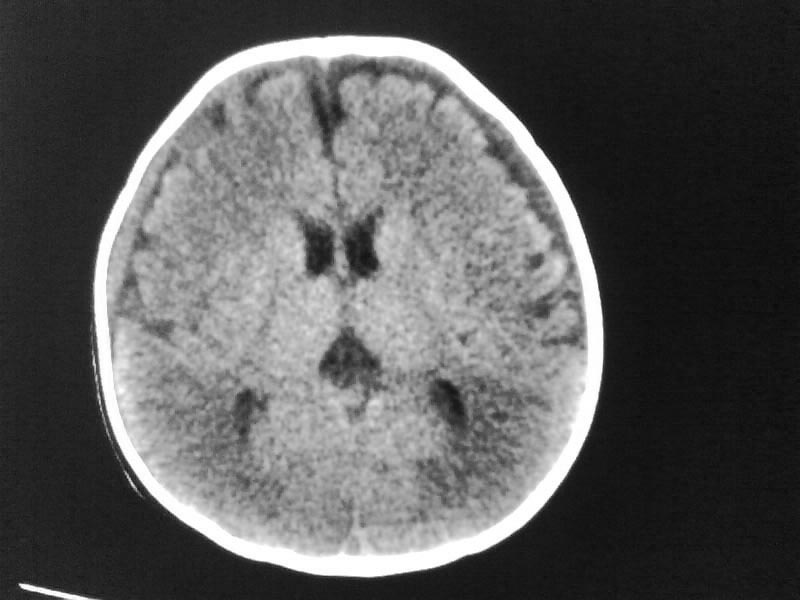

以下是引用小初学者在2009-4-15 10:26:00的发言:[br]考虑右侧额顶部硬膜下血肿。

以下是引用随光逐影在2009-4-15 17:59:00的发言:[br]1)右侧额颞顶部硬膜下血肿。2)外部性脑积水。